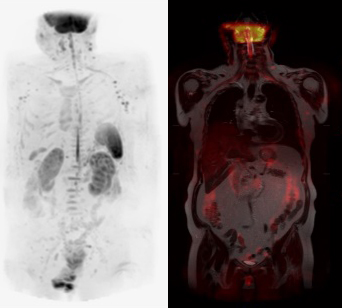

軽量であると共に、コイルサイズが長さ79cm幅66cmと、かなりの大判サイズのため有効感度面積が広く、柔軟性が高いので汎用性に富み、全身DWI含めた躯幹部の撮影から(図4、5)、肩関節などの四肢まであらゆる部位に使用が可能となっています。そのため部位によって使用するコイルの選択に迷う事がなくなり、患者へのコイル装着を容易に行うことができるようになりました。特に肩などの磁場不均一部位での検査でもAIR AAコイルの感度均一性が高いので、患者体位設定の不備による感度ムラが起きにくく、常にSNRの高い画像を提供可能となりました(図6)。

図5 全身DWI画像(左:MIP画像、右:Fusion画像)